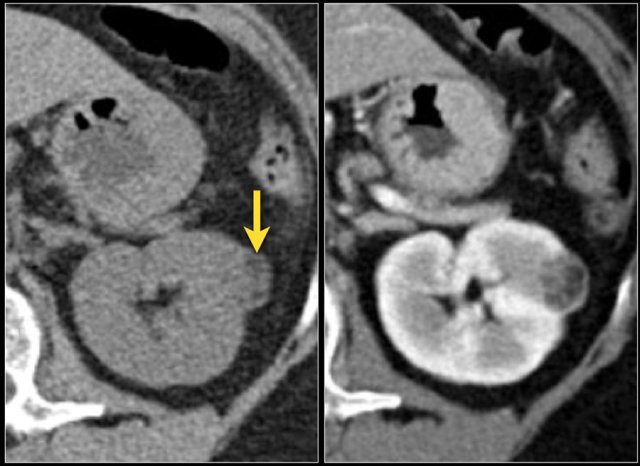

Here is another case.

In the nephrogenic phase one could argue there is a lesion in the left kidney.

In the corticomedullary phase however it is clear that this is a pseudotumor.